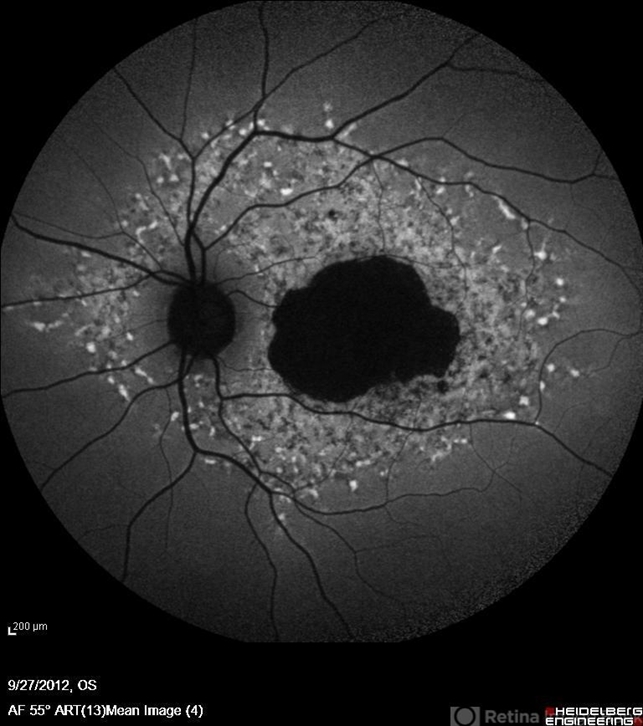

- Stargardt disease, autofluorescence imaging

- Nayereh Hadipoor, Negah Eye Center, Tehran

- Heidelberg Spectralis

- Autofluorescence imaging of the left eye of a 46-year-old man with decreased VA due to advanced Stargardt's disease.